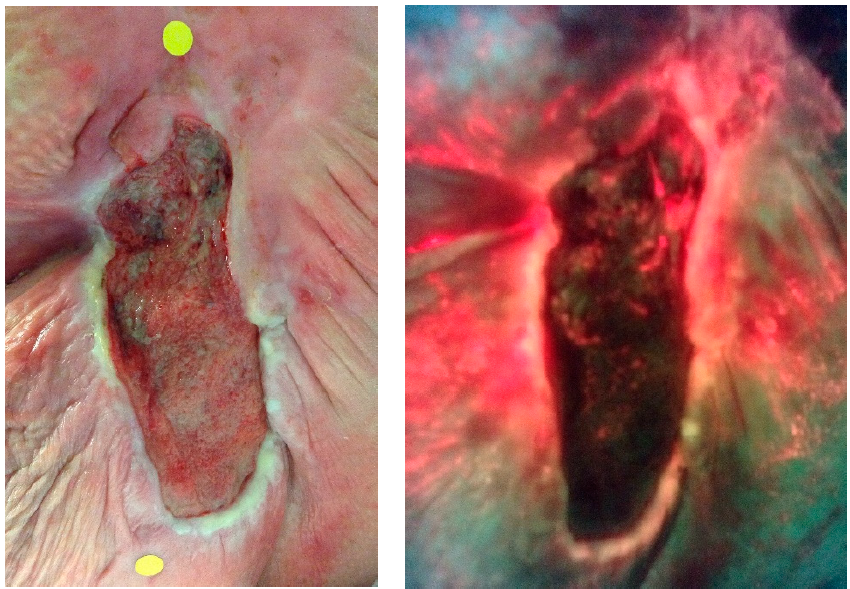

The clinical progression and wound healing rate of dehisced perineal tears healing by secondary intention: A prospective observational study

Okeahialam NA et al. Eur J OGRB 2022

Bacterial autofluorescence in infected perineal wounds: A prospective cohort study

Okeahialam NA et al. DMID 2022